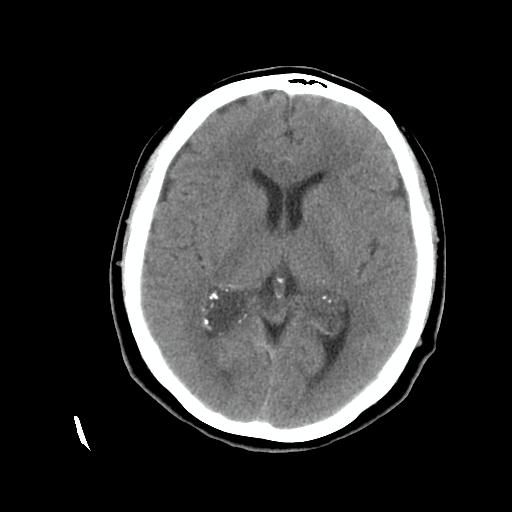

标题: CT24768:双侧脑室内囊性病变,主各位站友会诊。 [打印本页]

标题: CT24768:双侧脑室内囊性病变,主各位站友会诊。

患者女,62岁,临床提供头痛、头晕数月,无恶心及呕吐,近日加重。请各位站友看看,能否定为双侧脑室脉络丛囊肿,如果不能,应考虑什么?谢谢!

除了脉络膜丛囊肿外,枕叶内的片状钙化密度影,其周围无水肿,可能还要考虑血管畸形吧,建议增强扫描以明确诊断。